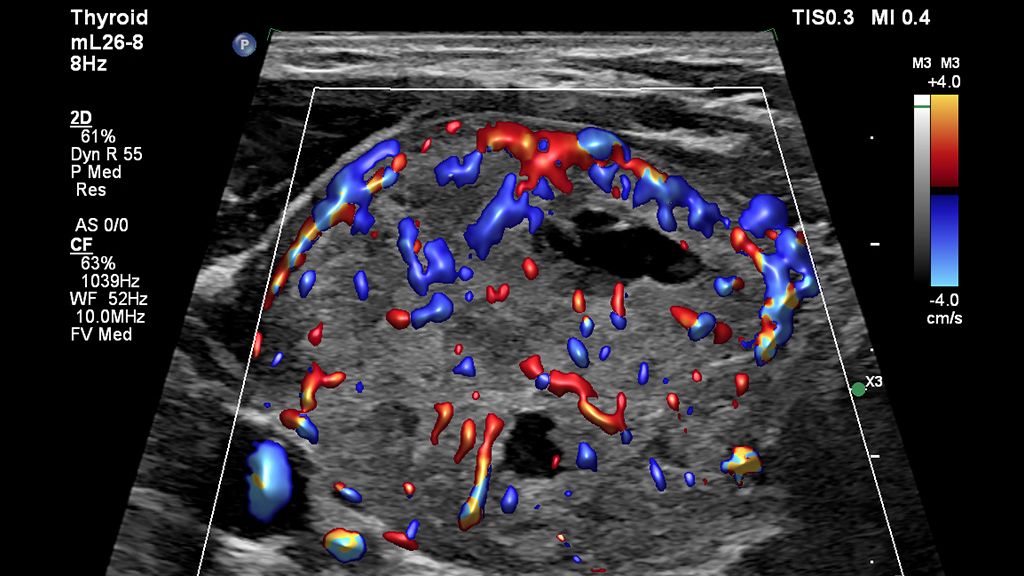

Dr Andrew McQueen of Freeman Hospital shares his experience working with the mL26-8 and eL18-4 ultra high-frequency linear transducers for neck ultrasound.

If we can increase our confidence in the subtle diagnosis at the time of scanning, we can triage the subsequent investigation pathway appropriately and prevent delayed diagnoses.